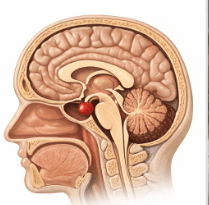

특히 뇌하수체처럼 좁은 공간에 발생하는 종양은 단순히 양성이라는 이유만으로 판단할 수 없습니다. 시신경을 누르고, 해면정맥동을 침범하고, 재발 가능성이 높다면, 그건 더 이상 ‘착한 종양’이 아닙니다.

뇌하수체는 우리 몸의 호르몬 조절을 담당하는 컨트롤 타워와 같습니다. 이곳에 생기는 종양은 의학적으로 세포의 증식 속도가 느린 편이라 대부분 ‘양성 신생물’로 분류됩니다. 주치의들 역시 수술이 잘 끝났고 생명에 당장 지장이 없다면 관례적으로 D35.2 코드를 부여하곤 하죠.

- 침윤성 성장(Invasion): 종양이 인접한 해면정맥동이나 경막, 심지어 뼈까지 갉아먹으며 자라고 있는지 확인해야 합니다. 이는 세포 모양과 상관없이 종양의 행동 양식이 악성임을 보여주는 강력한 증거입니다.

- 임상적 위험도: 시신경을 압박하여 실명 위기에 처했거나, 호르몬 과다 분비로 인해 신체 기능이 마비될 정도라면 이를 단순한 양성으로 치부해서는 안 됩니다.